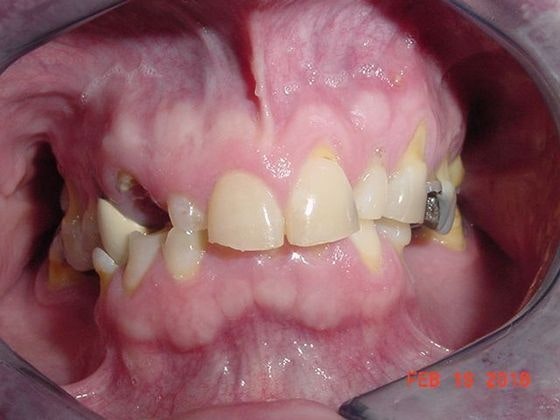

See One All-on-4 Patient's Results A True Dental Transformation

before dental implants

Before All-on-4 Vanessa came from Greenville, MS, for help with her smile. She was dealing with advanced dental decay as well as missing teeth and was ready for a change.

after dental implants

After All-on-4 After discussing her options, we gently extracted the compromised teeth and moved forward with All-on-4. She now enjoys a stunning, functional smile.